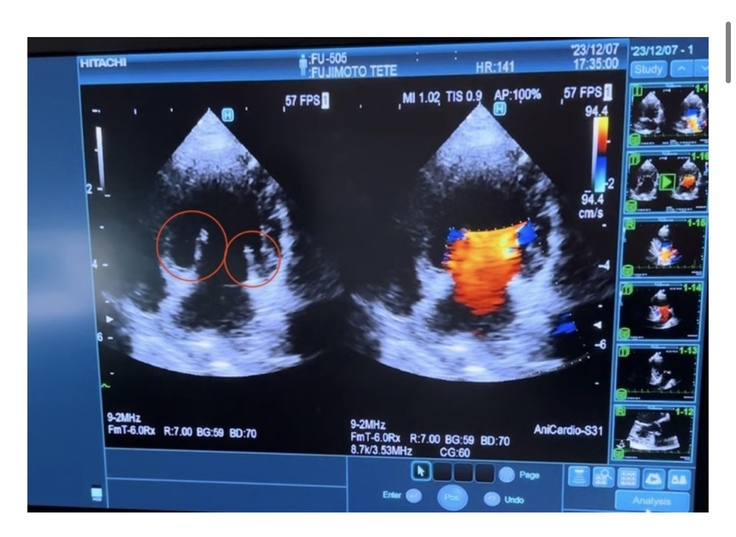

てっての心臓検査の画像です。レントゲン検査では、心臓が肥大し気管を圧迫していることが見て取れます。

獣医師によれば、下記画像の

左側の赤丸部分は便が正常に閉じていない状態、

右側の色付き部分は便が閉じないことによる血液の逆流を示す。

ということでした。